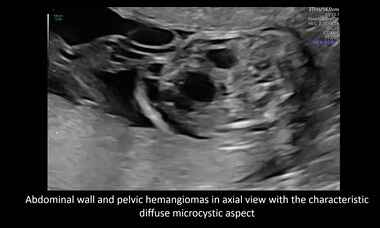

UOG Videoclip: Prenatal diagnosis of fetal diffuse hemangiomatosis: the central role of genetic counseling

New UOG Journal videoclip on the role of ultrasound and genetic counselling in fetal hemangiomatosis related to PIK3CA-related overgrowth syndrome.